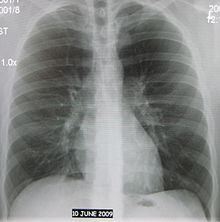

Abreugrafia

Criado por Manoel Dias de Abreu, foi indicado ao Prêmio Nobel em 1950. O Nome Popular ficou como Raio X.